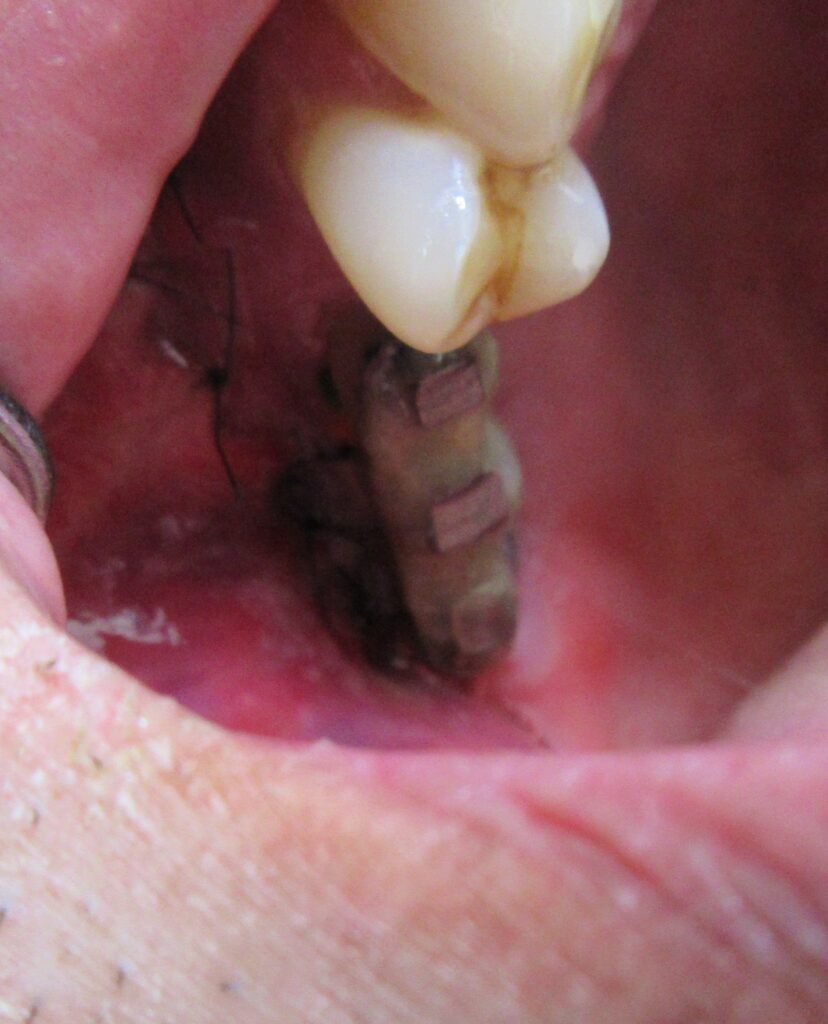

開けた穴に、専用道具を使ってネジを締めるように長さ2センチ程のインプラントを骨に埋め込んでいきます。

続けて他の歯も同じように植立していきます。

インプラントオペでは、複数本を植立する場合でも、当時進行はせず、1本ずつ同じ工程を繰り返して植立します。

しっかりとインプラント埋め込まれた後は、動揺がないか、噛んだ時に当たらないかなどを確認して、最後にパノラマ写真を撮影して今回のオペは終了となりました。